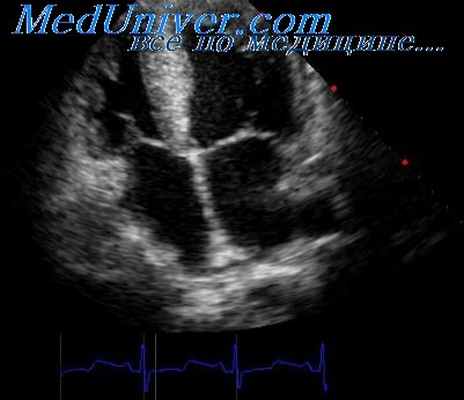

Цветовое допплеровское картирование является разновидностью ИВ допплерографии, при которой кровоток или движение миокарда изображаются разными цветами (обычно красным, синим и зеленым) или их комбинацией, что зависит от скорости, направления и наличия турбулентности.

В каждом участке изображения частотный сдвиг измеряется, преобразуется в цифровой формат, автоматически сопоставляется с заданной цветовой схемой (автокорреляция) и выводится на экран на фоне двухмерного изображения. При оценке кровотока в полостях сердца поток, направленный к датчику и имеющий положительный частотный сдвиг, кодируется оттенками красного. Кровоток, направленный от датчика и имеющий отрицательный частотный сдвиг, колируется оттенками синего.

Оценки в пределах каждого первичного цвета задаются высокими скоростями, не достигающими предела Nyquist. Когда скорость становится выше этого предела, появляется искажение цвета. Турбулентность отражает степень отклонения скоростей в определенной области от средней скорости и кодируется обычно оттенками зеленого.

В связи с этим аномальный кровоток легко распознать по комбинации многочисленных цветов, соответствующих направлениям, скоростям и степени турбулентности. Ширину и размер аномального внутриполостного кровотока используют для оценки степени регургитации на клапанах или выявления впутрисердечных шунтов.

Почти все структурные и гемодинамические сердечные аномалии нарушают кровоток и, следовательно, приводят к изменениям при цветовом допплеровском картировании. Его также используют для определения диастолической дисфункции и длительности фаз сердечного цикла. На рисунке продемонстрированы динамические изменения клапанной регургитации и гемодинамики, записанные с помощью допплерографии и цветового допплера.